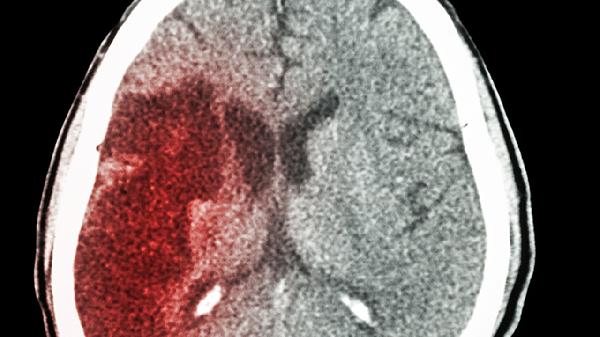

为什么越来越多的农村人得上脑梗死?医生:4个原因暴露真相

农村地区脑梗死发病率上升确实是一个值得关注的现象。这种现象背后隐藏着多重因素,让我们一起来剖析其中的关键原因。